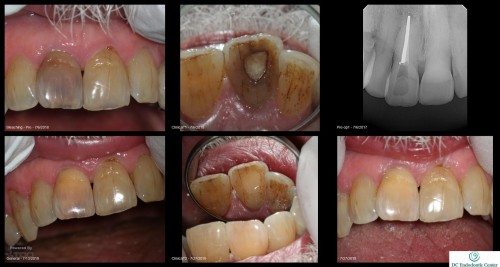

Apexogenesis

Very young 7 yo male.  Original injury Nov 2015. Tooth was restored/bonded and became symptomatic […]